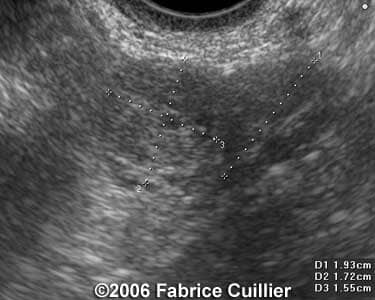

Case 1

case1b

case1a